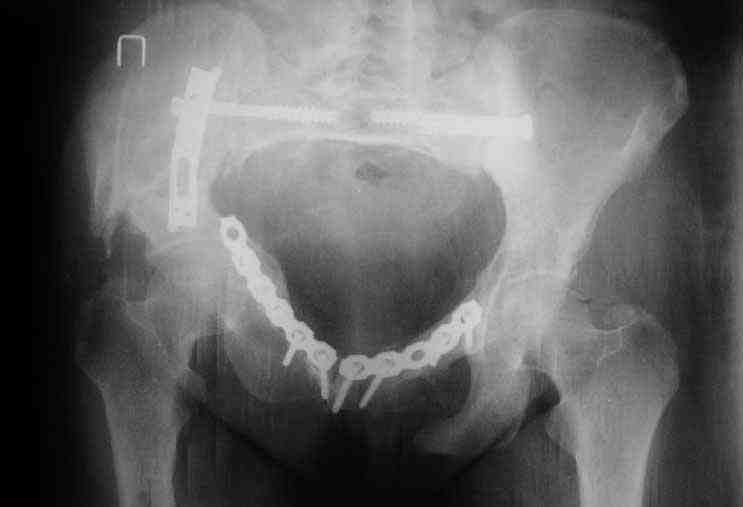

Снимки до лечения: